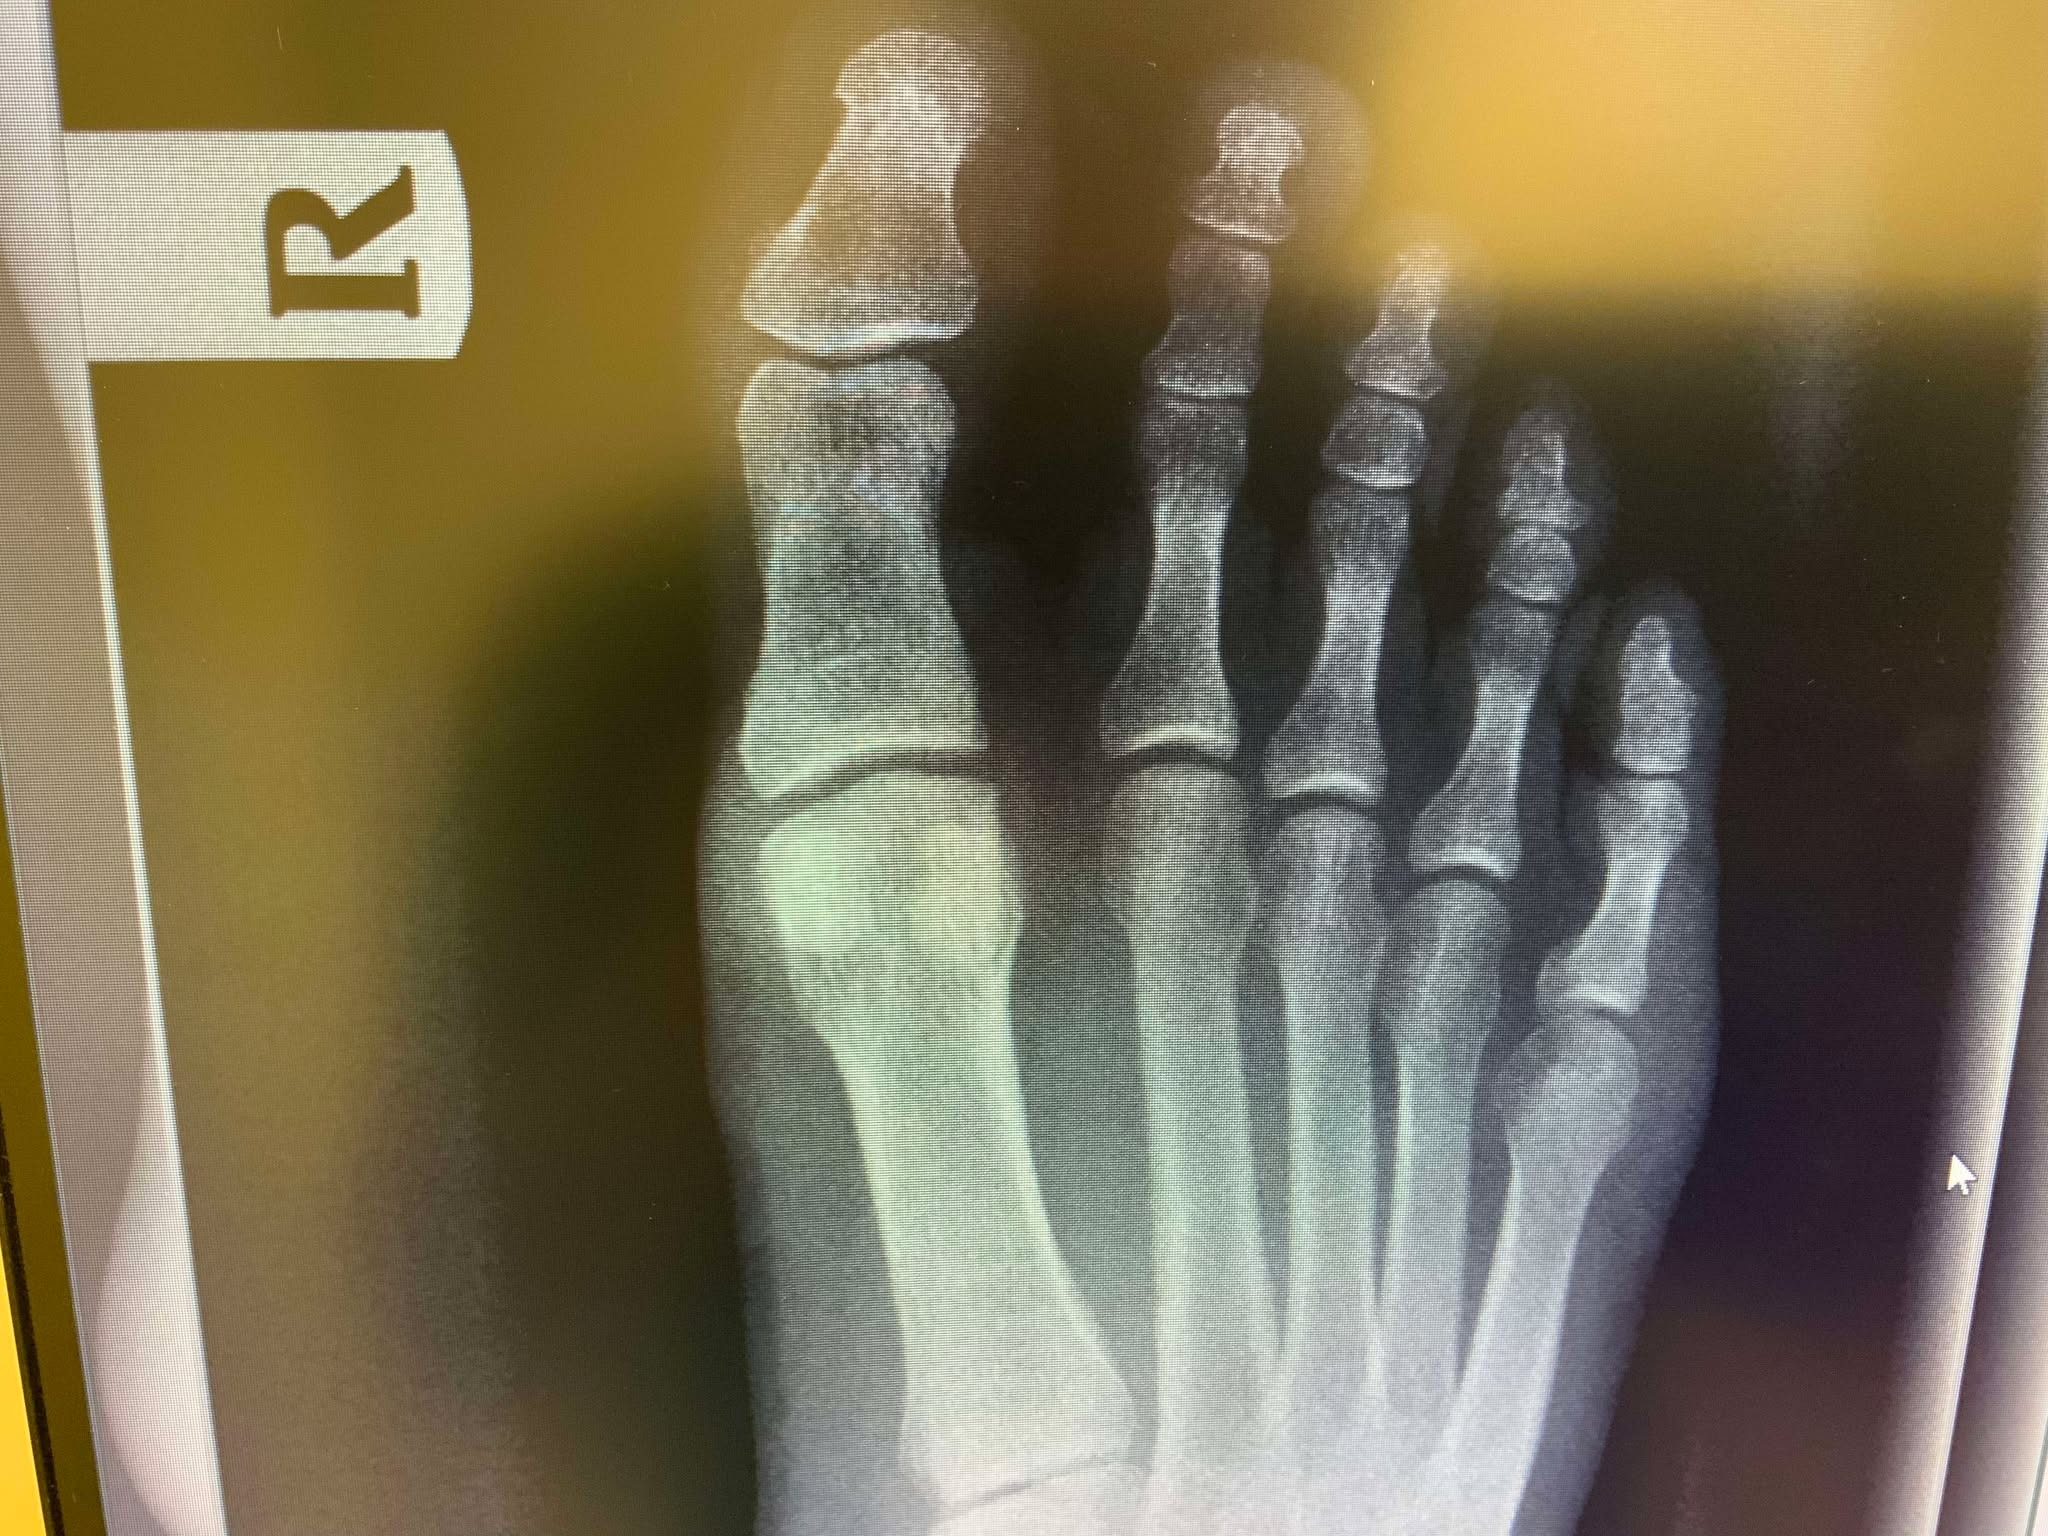

I'm an author and journalist with an amazing family and a small desert ranch in Southern California. I love our little hobby farm, but unfortunately it was one of our 250-lb goats that stepped on me almost nine months ago and broke a small bone in my right foot. My surgeon informed me that it hasn't healed, and that it won't heal, so he needs to remove the bone itself to keep the pain from lasting my entire life (fortunately, as he says, this bone is the tonsils of the toes, in that it is removable without ruining my ability to walk long term). I actually have health insurance, but the surgery is $18,000, and my plan only covers $10,000 of that. I'm expected to pay $8,000 up front at the time of surgery, which is in 10 days, and there are also special shoes and inserts, etc., I will need for recovery. In total, my share of the costs will be around $12,000. With the cost of maintaining about 100 total rescue animals on our ranch, I know I can't do that alone. I'm really hoping some of you out there are willing to chip in and make this a little easier. I sincerely appreciate all of you who read this, and those who contribute have my undying gratitude. Thank you all.